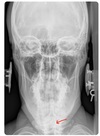

3

APOM ANATOMICAL LANDMARKS

maxillary sinus

29

frontal sinus

30

nasal aperature

31

nasal spine + septum

32

lower teeth

33

upper teeth

34

mandible

35

jugular process

36

A-P open mouth

rim of foramen magnum

37

anterior arch c1

38

posterior arch c1

39

A to P open mouth

lateral mass of c1

40

transverse process c1

41

medial inferior tip of occipital condyles

42

mastoid air cells

43

A-P open mouth view

pedicle shadow c2

44

spinous process c2

45

eop-iop

46

atlantal-axial joint space

47

vertebral bodies c2-c7

48

inferior articular surface c1

49

superior articular surface c1

50

A-P cervical

uncinate process of cervical vertebra

51

occipital-atlantal joint space

52

odontoid process